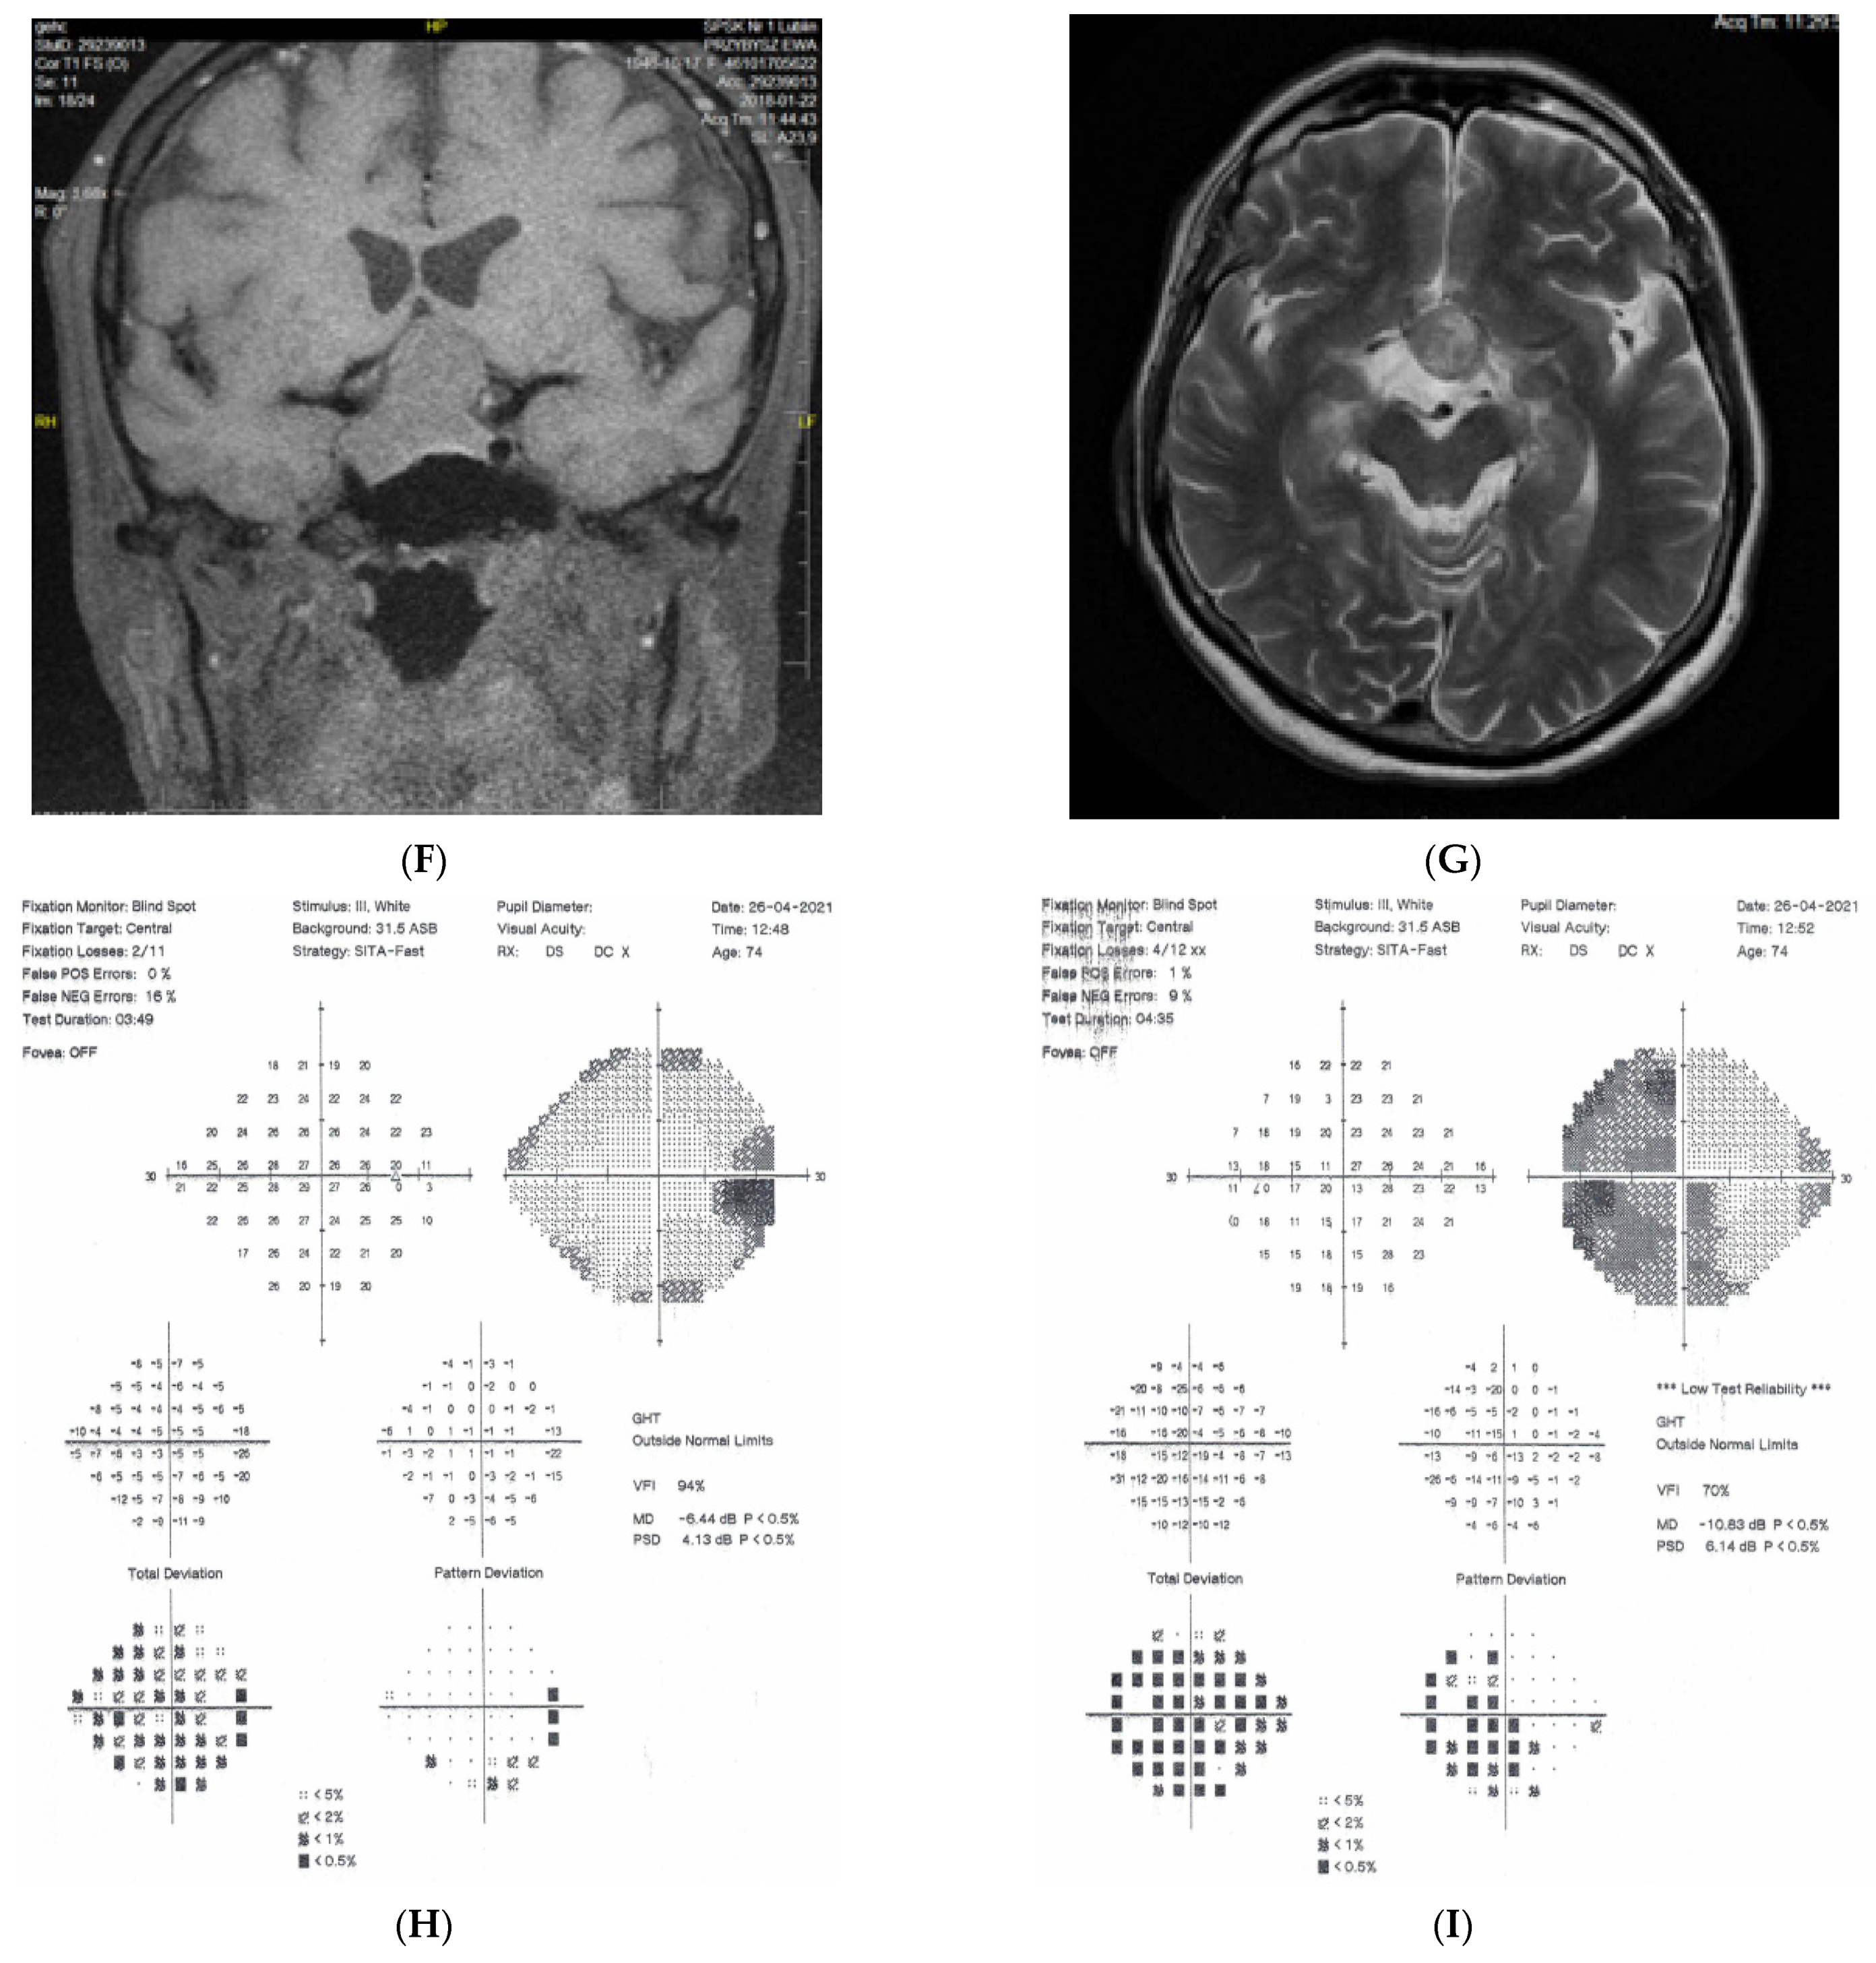

2.4. Case 4